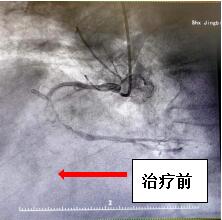

2024年3月24日,患者田某某,在家中突然感觉心前疼痛、气短,上腹部、剑突下疼痛,伴呕吐,当时来我院急救中心就诊,值班医师对其进行心电图检查,结果显示ST段抬高,立即请心血管内科医生进行会诊,考虑急性心肌梗死!建议住院进一步检查。办理住院后,对患者进行了进一步检查,经综合评估需对患者立即进行手术。但考虑患者年龄较大,随时有消化道、颅内出血风险。高龄患者血管脆性增加、动脉硬化严重,又突发急性心梗,手术风险极大,极有可能在手术过程中心脏破裂死亡。但不进行手术,进行保守治疗,随时可能出现心梗面积增大、严重心衰、恶性心律失常,也面临死亡风险。该如何抉择,患者病情极其危重,随时有生命危险。高四红主任医师带领心血管内科介入团队立即组织讨论,并向家属详细告知病情及手术风险,制定可行性治疗方案,经家属同意后,在导管室的全力配合下对患者进行冠脉造影术及支架植入术。手术过程中患者右侧锁骨下动脉严重迂曲,造影导管无法到达冠脉口,介入团队当机立断,改变导管路径,穿刺股动脉进行冠脉造影,造影结果发现患者前降支近中段重度狭窄,右冠远端弥漫性狭窄,最严重处99%狭窄,评估血管情况明确患者系多支病变,心血管内科介入团队顶住压力,尽最大努力缩短手术时间,经过1小时努力,患者右冠血流恢复,治疗效果显著,胸痛、气短缓解。术后通过心内科医护人员的精心治疗,患者康复出院。